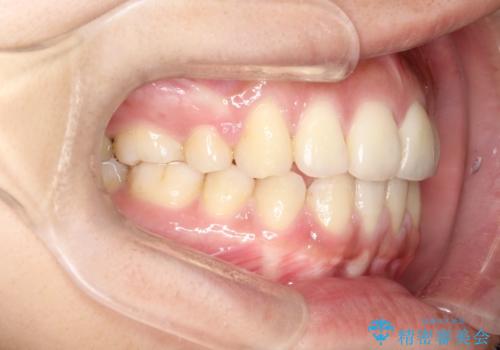

横顔をすっきりさせたい 下の前歯が1本少ない方の変則的な抜歯矯正

口元の突出感がありと、下顎の前歯が1本欠損していました。

上顎の前から両側の前から4番目の歯と、下あごの前歯を1本抜歯して、口元をすっきりさせる計画としました。